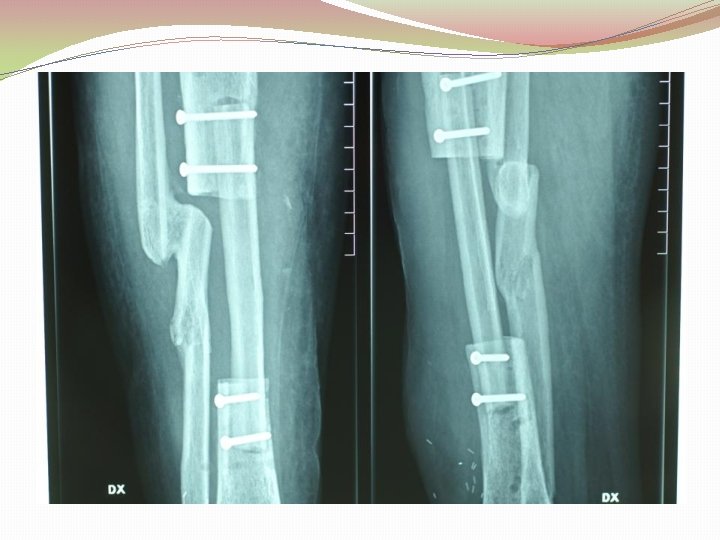

Ķirurģiska ārstēšana Osteomielīta pacientiem jāveic radikāls debridement ķirurģiski, kas ietver visu procesā iesaistīto audu rezekciju: �Mīksto audu rētas rezekcija �Cīpslu kalcinātu rezekcija �Distantu sekvestru rezekcija �Kaula rezekcija līdz vizuāli veseliem audiem – readzama punktveida asiņošana ´Paprika sign’. Bogdan Maciuceanu, Lucian Jiga, Alexandru Nistor, Jenel Marian Pastrascu, Mihail Ionac Chronic Osteomyelitis of Long Bones Timisoaral Medical Jornal, 2005

Ķirurģiska ārstēšana Veiksmīgas ķirurģiskas ārstēšanas stūrakmens ir mirušas telpas ‘Dead space’ aizpildīšana, kas izveidojas pēc debridemet veikšanas Brad Parsons, Elton Strauss, Surgical management of chronic osteomyelitis, The American Journal of Surgery 188 (Suppl to July 2004) 57 S– 66 S

Debridement Os konstrukciju evakuācija Biopsija un mikrobioloģija Dobuma slēgšana Antibakteriāla terapija Stabilizācija (Ārējā fiksācijas aparāts) Maina vai apstiprina antibakteriālo terapiju Mīksto audu rekonstrukcija 6 nedēļas antibakteriāla terapija (pēc debridement) Pseidartroze Konsolidācija Atkārtot ārstēšanu Luca Lazzarini, Jan T. Mader, Joson H. Calhaun Osteomielitis in Long Bone, The journal of bone&joint surgery, Volume 86 A, nr 10, 2004